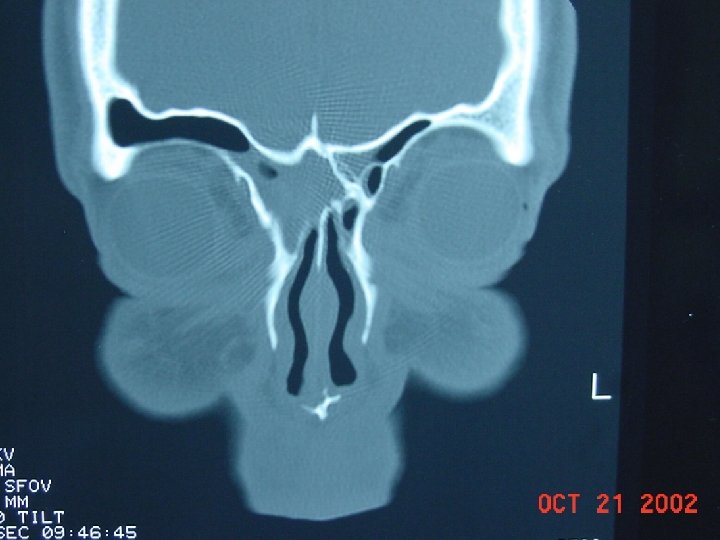

Diagnosis • Based on clinical signs and symptoms • Physical Exam: Palpate over the sinuses, look for structural abnormalities like DNS. • X-ray sinuses: not usually needed but may show cloudiness and air fluid levels • Limited coronal CT are more sensitive to inflammatory changes and bone destruction

Coronal computed tomographic scan showing ethmoidal polyps. Ethmoid opacity is total as a result of nasal polyps, with a secondary fluid level in the left maxillary antrum.